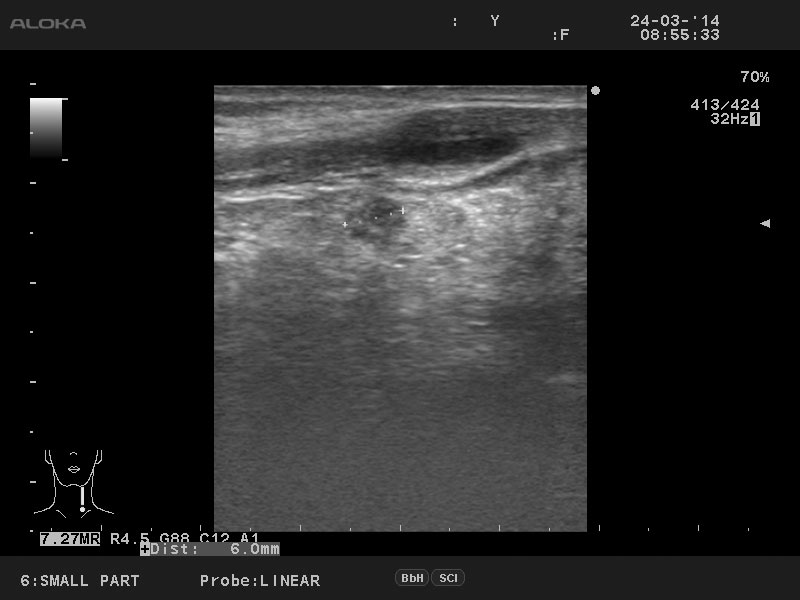

Мужчина 50 лет, жалоб нет.

aml_20140324_SMALL-_PART_00.jpg

Диагноз доказан цитологически.